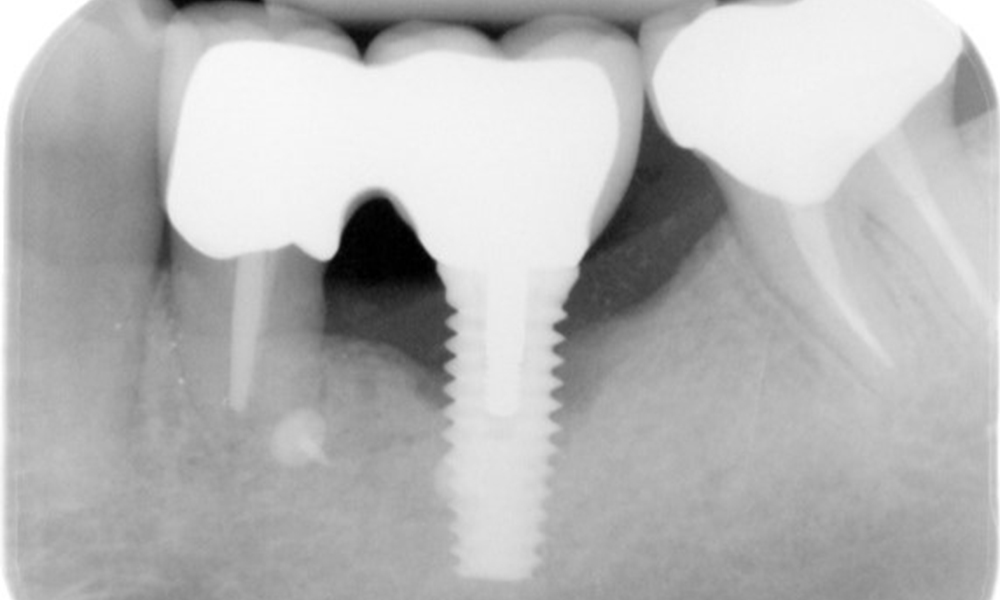

The X-ray images show the progression of bone loss.

The X-ray images show the progression of bone loss. OPG from 29.06.2020 (left) and OPG from 26.02.2024 (right).

The X-ray images show the progression of bone loss in the area of the implant in region 36: dental film from 11.02.2021 (left) and dental film from 18.01.2024 (right).